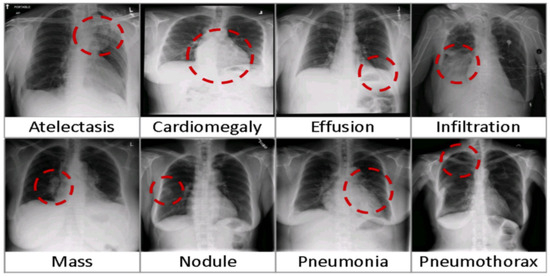

5. X-ray-14 Images Diagnosis

The Chest X-ray14 dataset encompasses a comprehensive collection of 112,120 frontal chest X-ray images sourced from 30,805 patients. This extensive compilation was meticulously assembled leveraging radiological summaries archived within hospital-based image storage and communication frameworks, subsequently refined through advanced natural language processing techniques. Each image within the dataset may exhibit signs of one or several common pulmonary conditions, with images labeled as “Normal” indicating a complete absence of detectable thoracic abnormalities (refer to Figure 9 for an illustration). The dataset is accessible for research and application at the following URL: https://nihcc.app.box.com/v/ChestXray-NIHCC (accessed on 2 February 2024).

Figure 9.

Frequent pulmonary conditions identified through chest X-ray imaging [51].